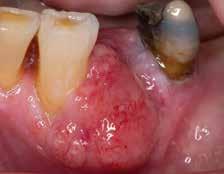

Abb. 6: Intraorale Ansicht Unterkiefer nach Tumorresektion, Deckung mit Zungenlappen und nach Beschliff

Das Tumorboard empfahl eine chirurgische Tumorresektion, seitliche Halsdissektion (links) und die Deckung mit einem Zungenlappen (Abb. 6). Ein Teil des Alveolarfortsatzes mit dem Tumor inklusive dreier Zähne (31, 32, 33) wurde reseziert. Makroskopisch zeigte sich ein maximal 1 cm breiter bis an das Periost reichender Tumor, ohne Infiltration des Kieferknochens. Insgesamt sechs resezierte regionale Lymphknoten zeigten reguläre Architektur. Mikroskopisch zeigte sich ein eindeutiger Übergang des regulären Epithels mit Formationen eines invasiv wachsenden, malignen epithelialen Tumorgewebes mit nestund strangartiger Architektur. Der Tumor zeigte eine maximale Ausdehnung von 2,2 cm bei einer Tiefenausdehnung von 1 cm.

Der Patient wurde im Zuge der Tumornachsorge wieder an der Universitätszahnklinik Wien vorstellig. Am Beginn der prothetischen Fallplanung wurden montierte Situationsmodelle erstellt und ein aktueller Röntgenstatus erhoben. Intraoral bestätigte sich, dass der resezierte Bereich mittels eines Zungentransplantates gedeckt wurde.

Modellgussprothesen für den Oberkiefer und den Unterkiefer hatte, wurden diese herangezogen und als Immediatersatz erweitert sowie unterfüttert. Während der Planung entschied sich das behandelnde Ärzt:innen-Team sowohl im Ober- als auch Unterkiefer für eine teleskopierende Metallgerüstprothese. Zahn 11 wurde mittels Adhäsivtechnik aufgebaut und darüber hinaus für Zahn 21 eine Einzelzahnzirkonkrone geplant. Um eine adäquate Retention der Kronen gewährleisten zu können, wurden an fünf Zähnen gegossene Stiftaufbauten eingegliedert (Abb. 6 u. 7).